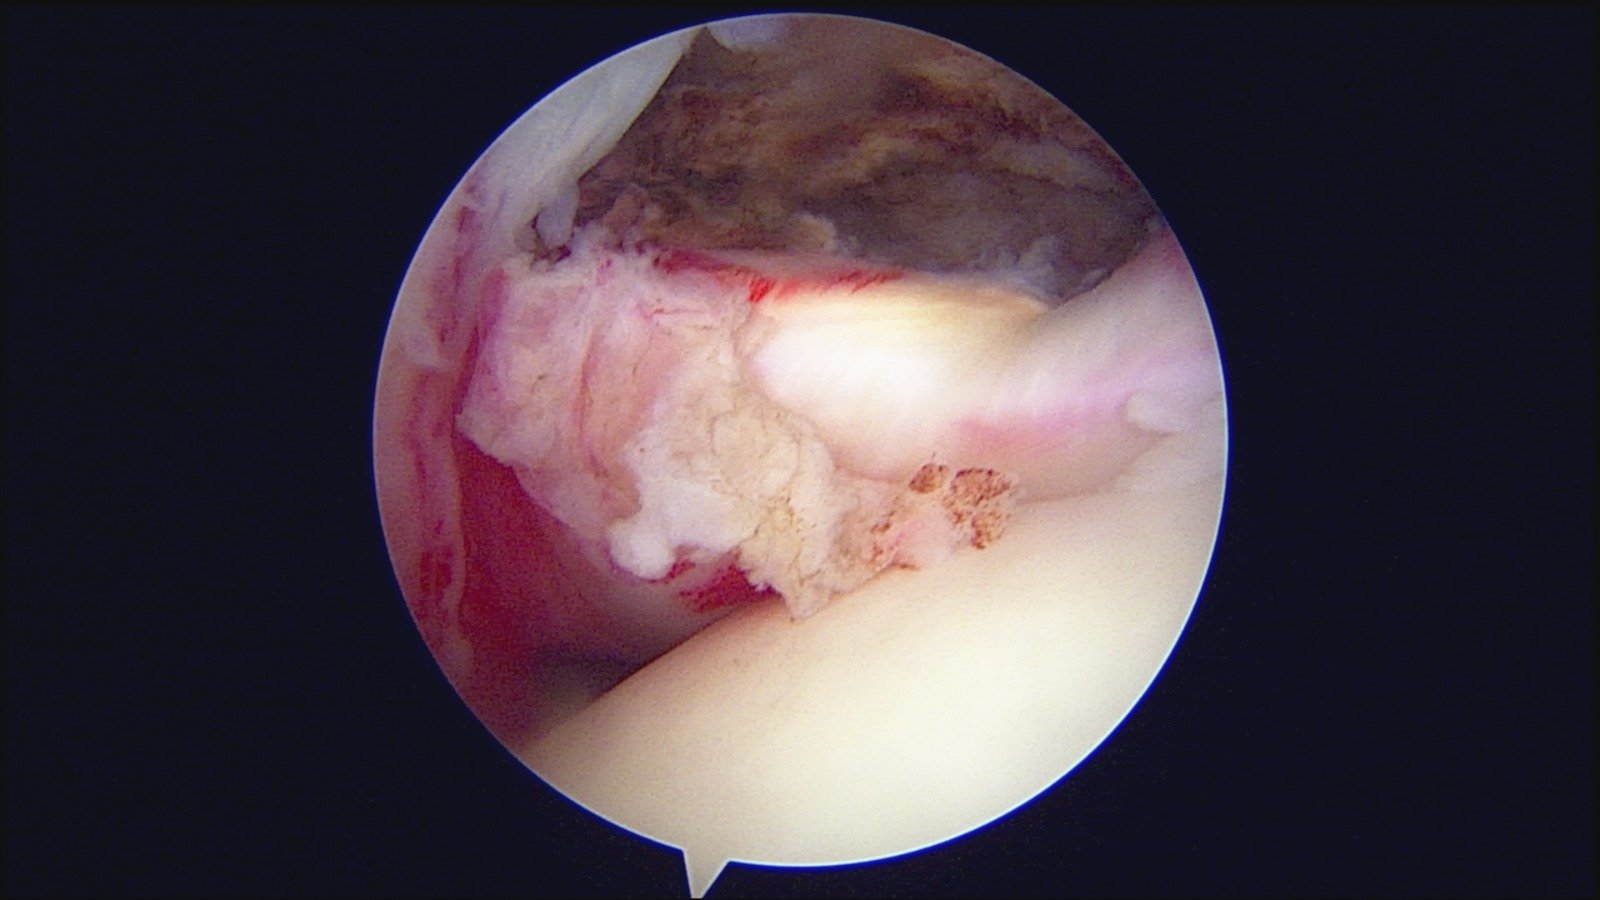

GalleryShoulder rotator cuff repair Meniscus root repair Meniscus repair Bankart repair for recurrent shoulder dislocation ACL reconstruction Machines Instruments